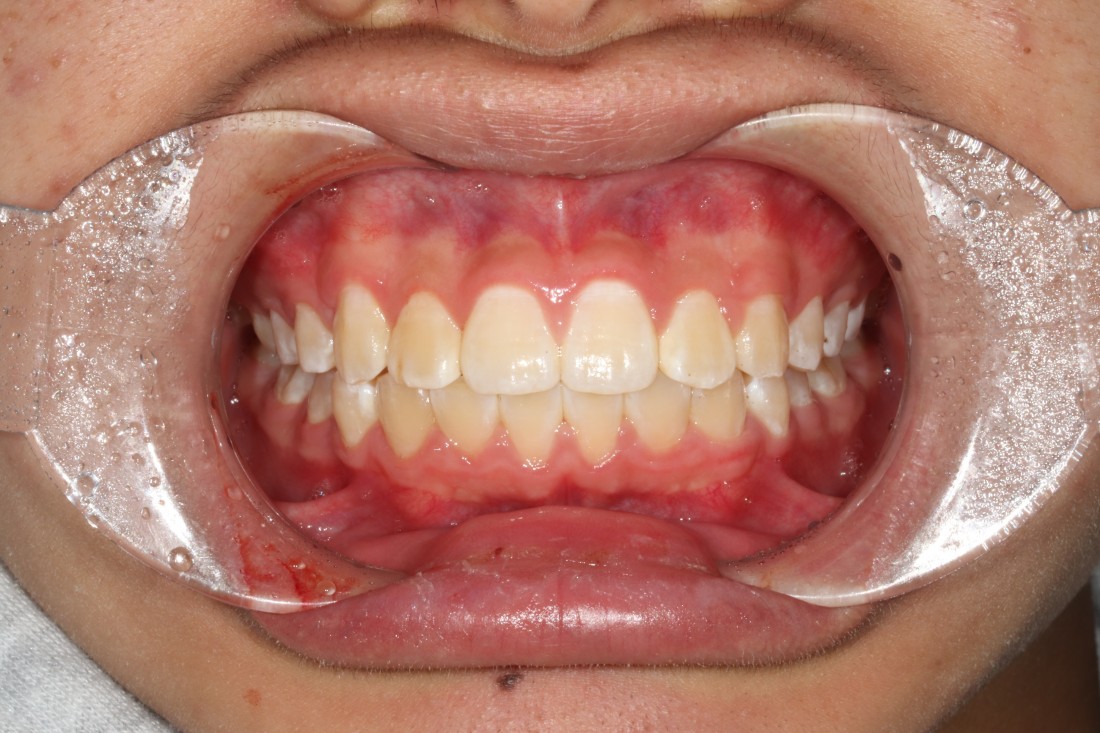

10대 청소년 학생들을 만나다보면

다른 사람들과 마주치거나 대화하는 것도

불편해하는 경우들이 보이는데요.

교정진료 역시 조용한 공간에서

프라이빗하게 받고 싶어하는

경우들이 더 많은 것 같습니다.